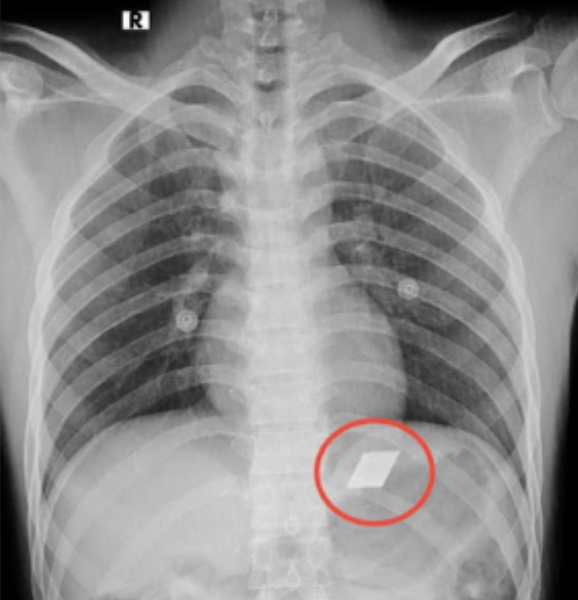

Bệnh viện Đa khoa tỉnh Bình Dương đã tiếp nhận một trường hợp hợp hi hữu nam bệnh nhân 26 tuổi nhập viện trong tình trạng nuốt nhiều dị vật kim loại sắc nhọn, bao gồm dao rọc giấy và dao lam.